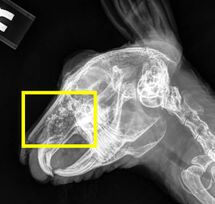

- Allison Zwingenberger. (2017). Radiographs of a 5-year-old rabbit with respiratory distress and nasal discharge found with a mucinous adenocarcinoma and metastatic disease to the lung upon necropsy (RIP)